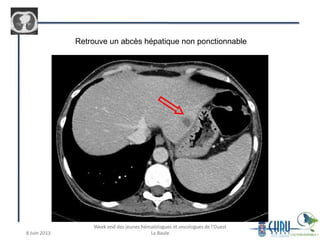

Retrouve un abcès hépatique non ponctionnable

• 12 joursplus tard: – Sepsis sévère, T°C = 41°C – Ambisome + vanco+ tienam – Persistance de la fièvre 1 mois d’hospitalisation => mise en évidence de BAAR dans le LBA Contrôle des BK crachats positif Début d’une quadrithérapie tuberculeuse Obtention d’une apyrexie, mais après 1 semaine recrudescence fébrile => TDM corps entier

Retrouve un abcèshépatique non ponctionnable